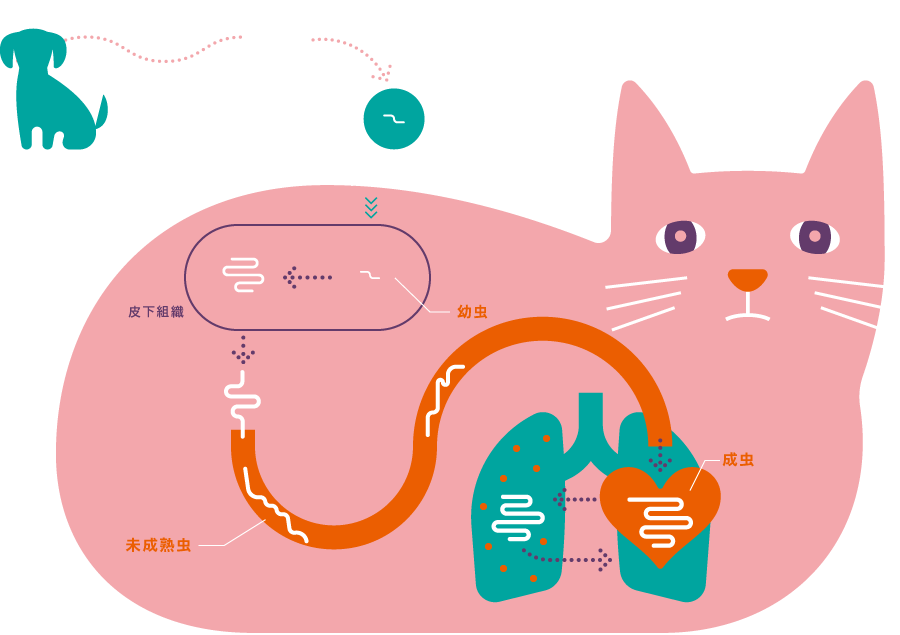

フィラリアの生態を知ろう

ねこの体内での一生

フィラリアの成長はいくつかのステージに分かれています。

- 5肺に移動

一度心臓を通り、肺へ移動。肺に炎症を引き起こします。また、未成熟虫は肺の中でまれに成虫へと成長します。

ねこのフィラリア症から起こる咳などの呼吸器関連の症候群は、HARD(Heartworm Associated Respiratory Disease=犬糸状虫随伴呼吸器疾患)と呼ばれています。

主にフィラリア感染犬の血液を吸った蚊がねこの血液を吸ったときに、フィラリアの幼虫がねこの体内に侵入し、感染します。